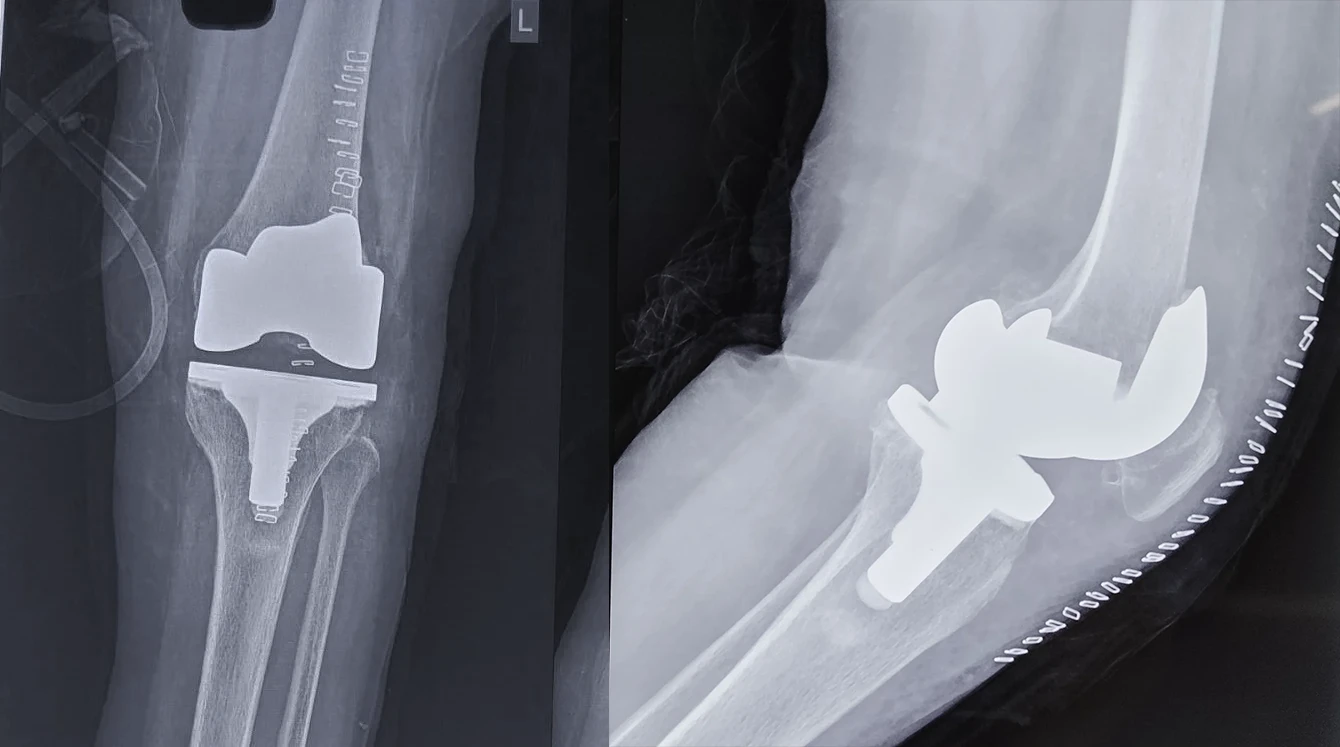

Rheumatoid Arthritis with Synovial Hypertrophy

Pre-Op X-Ray

Post-Op X-Ray